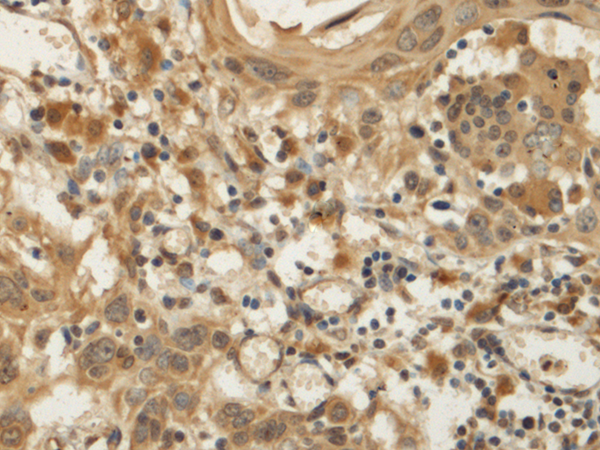

IHC positive control: |

Human tonsil and Human esophagus cancer |

IHC Recommend dilution: |

200-400 |